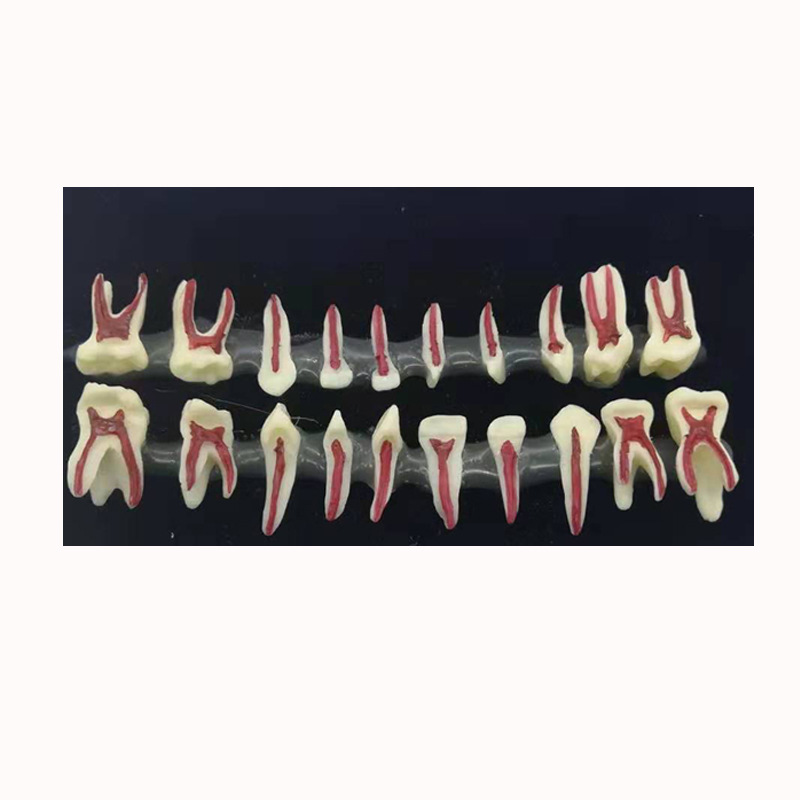

儿童牙齿剖面模型 医患沟通乳牙牙粒医患沟通演示 口腔乳牙